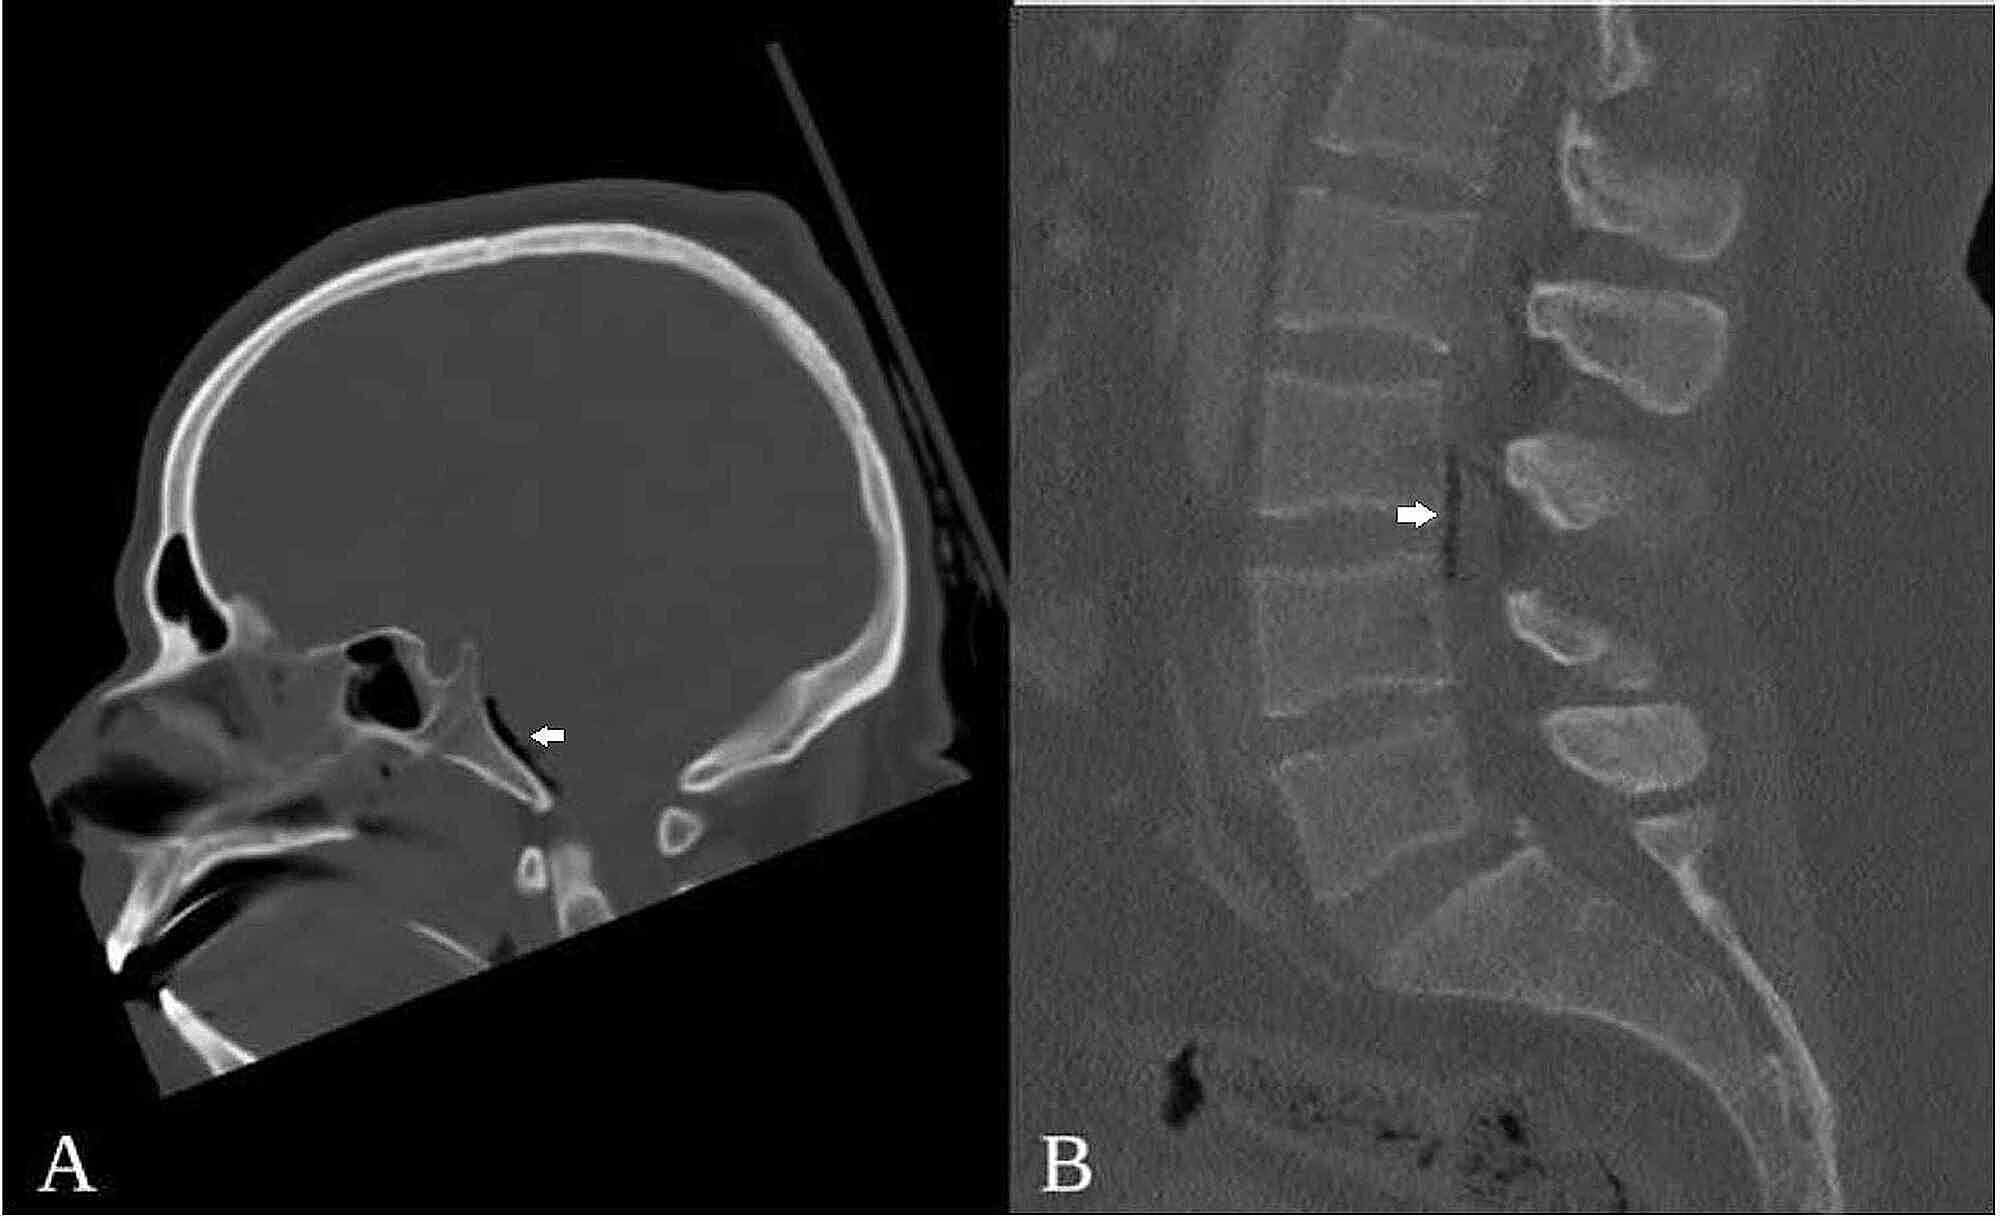

A 43yearold patient diagnosed with multiple basilar skull fracture Basilar Skull Fracture Pneumocephalus — the main cause of pneumocephalus in 75% of patients is neurotrauma, especially with the presence. basilar skull fracture, pneumocephalus. — a basilar skull fracture is a variant of skull fracture occurring at the base of the skull that can be missed on a ct. when pneumocephalus is suspected, ct can play a vital role in. Basilar Skull Fracture Pneumocephalus.

Initial noncontrasted CT brain, showing the basilar skull fracture Basilar Skull Fracture Pneumocephalus basilar skull fracture, pneumocephalus. — the main cause of pneumocephalus in 75% of patients is neurotrauma, especially with the presence. — basilar skull fractures are commonly encountered in the trauma setting. — a basilar skull fracture is a variant of skull fracture occurring at the base of the skull that can be missed on a ct.. Basilar Skull Fracture Pneumocephalus.